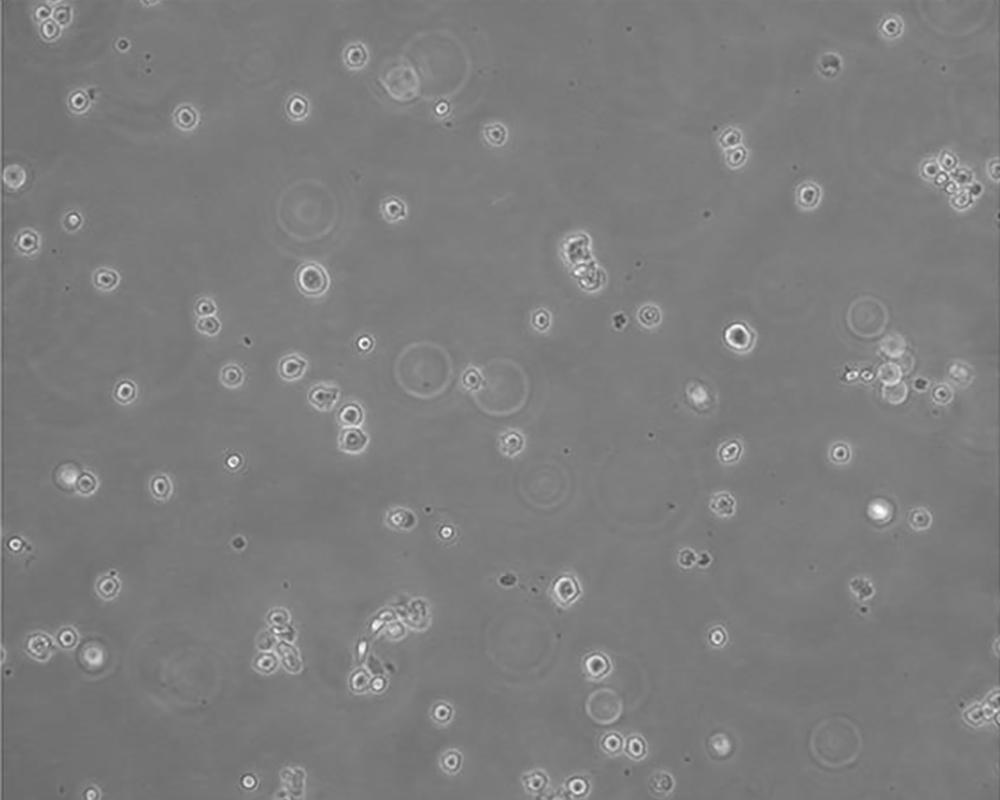

生長特性 suspension

形態特征 lymphoblast

細胞描述 該細胞來源于多發性骨髓瘤男性患者,表達IgG,分泌IL-6。